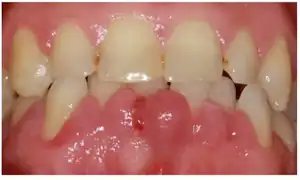

Felodipine can exacerbate gingivitis.[3]